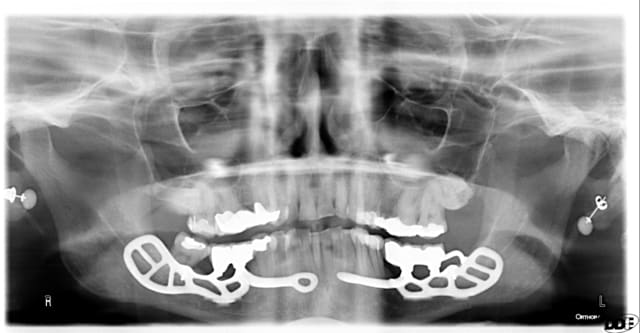

Sous-périosté placé en 2011, le secret c'est de le rendre rigide pour permette son intégration... formation osseux aux niveau des interstices où le périoste est soulevé.

ps. ne pas me parlé des boucles d'oreilles, merci